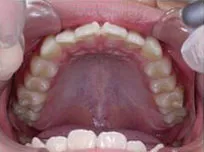

以下、当院で実施した床矯正の症例となります。

症例1

| 治療期間 | 11ヶ月(2021年6月〜2022年5月) |

| 費用 | 495,000円(税込) |

| リスクや副作用 | 成長期が終わった18歳以降に、2期矯正が必要になることがある |